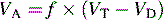

Normal tidal volume during spontaneous respiration is approximately 6 to 7   cc/kg. Approximately 70% of tidal volume reaches the alveolar space, and 30% fills the conducting airways. The latter volume is called the anatomic dead space (VD) and is typically approximately 2 to 3   cc/kg body weight. The anatomic dead space is the gas that remains in the conducting airways and does not participate in gas exchange. The remaining 70% of the volume that actually reaches the alveolar space is referred to as alveolar ventilation (VA). Alveolar ventilation can be estimated by subtracting the anatomic dead space from the tidal volume (VT):

image

For example, if the tidal volume is 100   mL, respiratory rate is 30/min, and the anatomic dead space is 20   mL, then alveolar ventilation would equal 30  ×  (100  −  20), or 2400   mL/min. Alveolar ventilation is always less than minute ventilation.